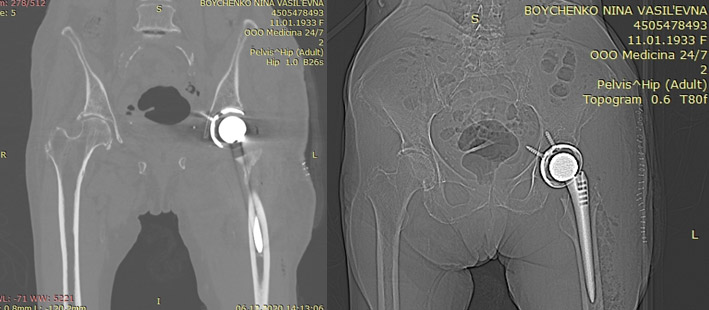

Пациентка Н.В. 88 лет

Диагноз:

субкапитальный перелом шейки бедра слева

Операция:

эндопротезирование левого тазобедренного сустава